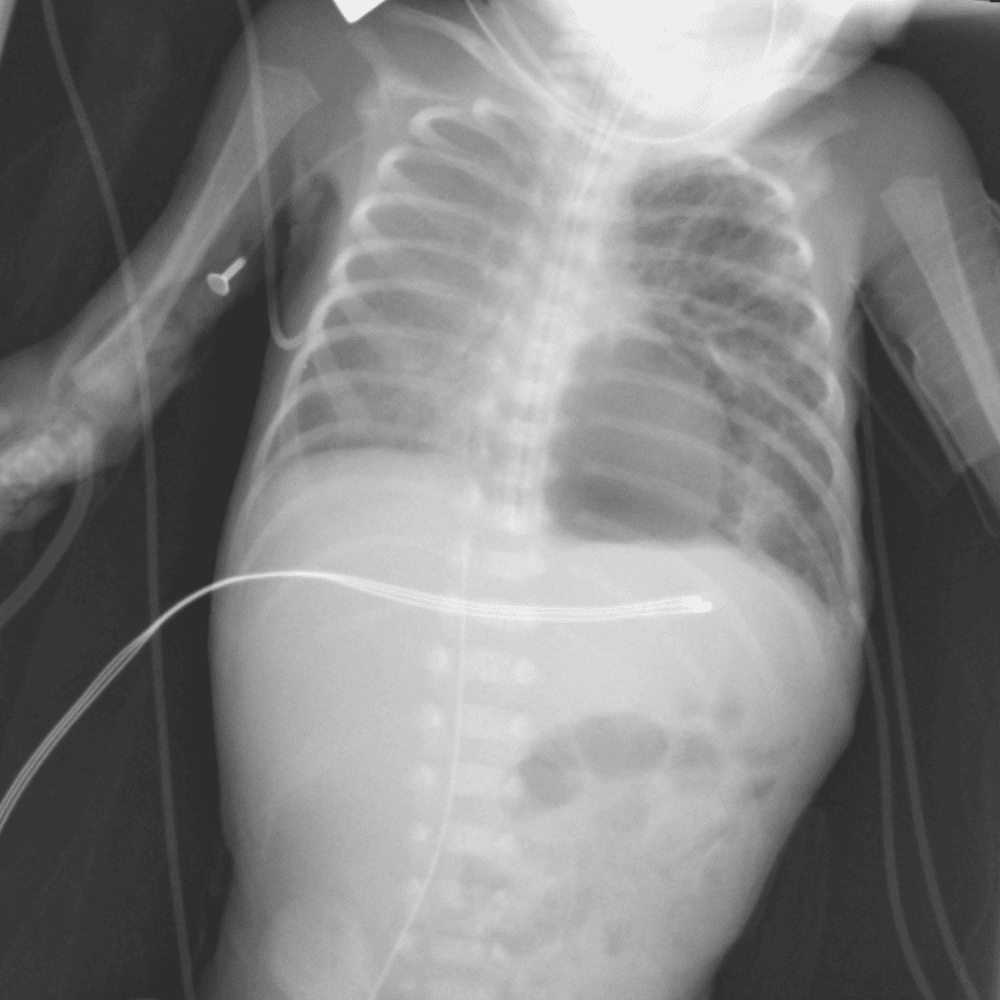

Peds Chest

Practice

Simulates call by including subtle or difficult cases and some normals.

50 cases